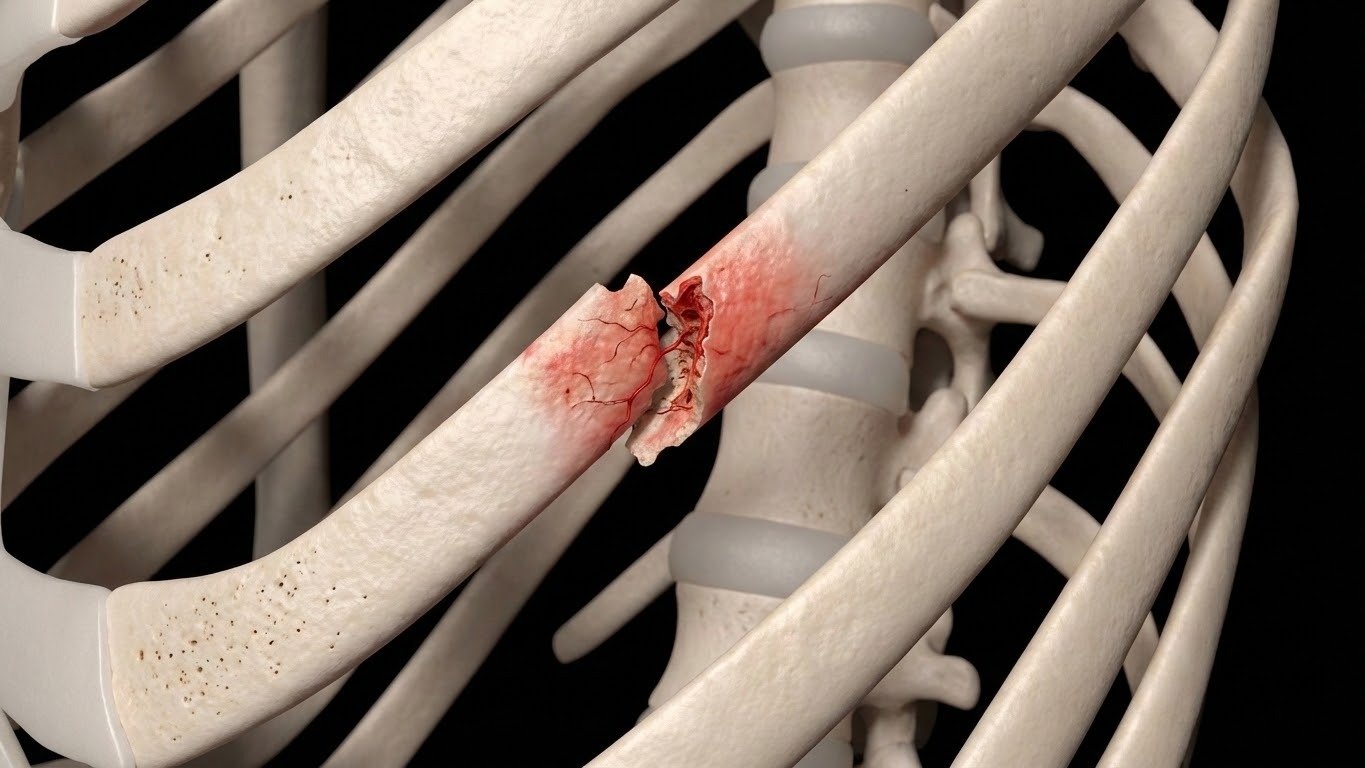

Die Herausforderung bei der Versorgung von Rippenfrakturen

Rippenfrakturen gehören zu den häufigsten Thoraxverletzungen und gehen oft mit starken Schmerzen, eingeschränkter Atmung und begrenzter Mobilität einher.

In der traditionellen klinischen Praxis stützt sich die konservative Behandlung in der Regel auf Analgetika und Ruhe, lässt jedoch eine wirksame externe Stabilisierung der frakturierten Rippensegmente vermissen. Ohne Stabilisierung bleiben die Patienten anfällig für schmerzhafte Mikrobewegungen beim Atmen, Husten oder bei körperlicher Aktivität.

Diese instabilen Rippenbewegungen verlängern nicht nur die Genesungszeit und verringern die Lebensqualität, sondern erhöhen auch das Risiko für schwerwiegende respiratorische Komplikationen wie Atelektasen und Pneumonien erheblich. Das Schließen dieser Versorgungslücke ist entscheidend für die Verbesserung der Patientenergebnisse und die Gewährleistung einer sichereren und schnelleren Rückkehr in den Alltag.